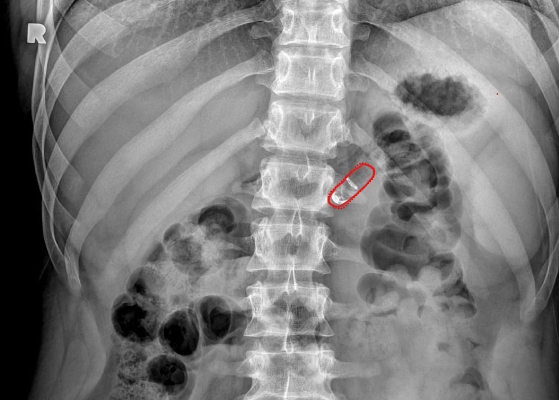

Rani Therapeutics’ approach is based on inherent properties of the gastrointestinal tract. An injecting mechanism in their pill is surrounded by a pH-sensitive coating that dissolves as the capsule moves from a patient’s stomach to the small intestine. This helps ensure that the pill starts injecting the medicine in the right place at the right time. Once there, the reactants mix and produce carbon dioxide, which in turn inflates a small balloon that helps create a pressure difference to help inject the drug-loaded needles into the intestinal wall. “So it’s a really well-timed cascade of events that results in the delivery of this needle,” said Imran.

Despite its somewhat mechanical procedure, the pill itself contains no metal or springs, reducing the chance of an inflammatory response in the body. The needles and other components are instead made of injectable-grade polymers, that Imran said has been used in other medical devices as well. Delivering the injections to the upper part of the small intestine also carries little risk of infection, as the prevalence of stomach acid and bile from the liver prevent bacteria from readily growing there.